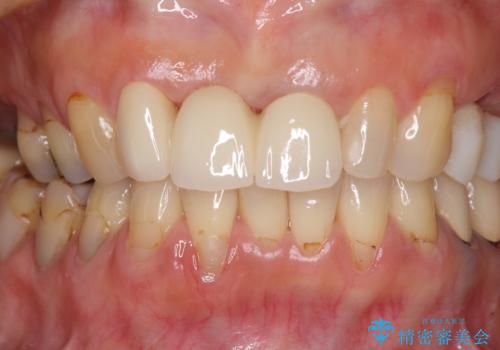

折れてしまった前歯 オールセラミックブリッジで自然な口元に

折れた前歯を抜歯すると、歯肉が痩せてしまい、ブリッジの形態の審美性が失われることがあります。仮歯を調整することで審美回復が必要であるか判断しますが、今回は歯肉移植を行うことなく補綴治療を行いました。